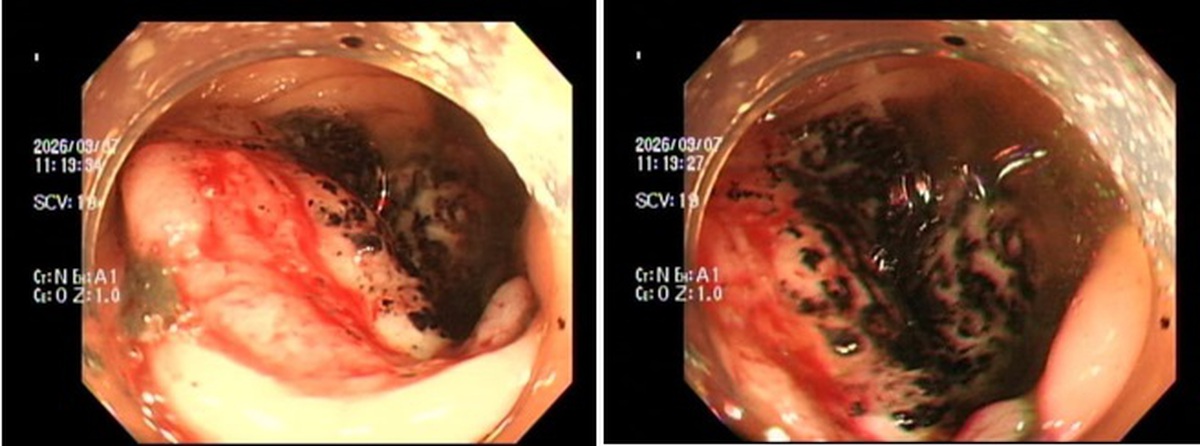

Tháng 1 năm nay, ông Từ (56 tuổi, sống tại thành phố Tuyền Châu, tỉnh Phúc Kiến, Trung Quốc) cùng vợ đi kiểm tra sức khỏe định kỳ tại bệnh viện địa phương. Kết quả nội soi dạ dày - thực quản khiến cả hai sốc nặng: cả hai đều được chẩn đoán mắc ung thư thực quản. May mắn là bệnh được phát hiện sớm, chưa có dấu hiệu di căn.

Sau khi đánh giá tình trạng bệnh, các bác sĩ đã chỉ định phẫu thuật nội soi trung thất để điều trị triệt căn ung thư thực quản cho cả hai bệnh nhân. Chỉ 5 ngày sau mổ, hai vợ chồng đã có thể xuất viện, sau khoảng một tuần phục hồi đã rút ống nuôi ăn và dần trở lại chế độ ăn bình thường.